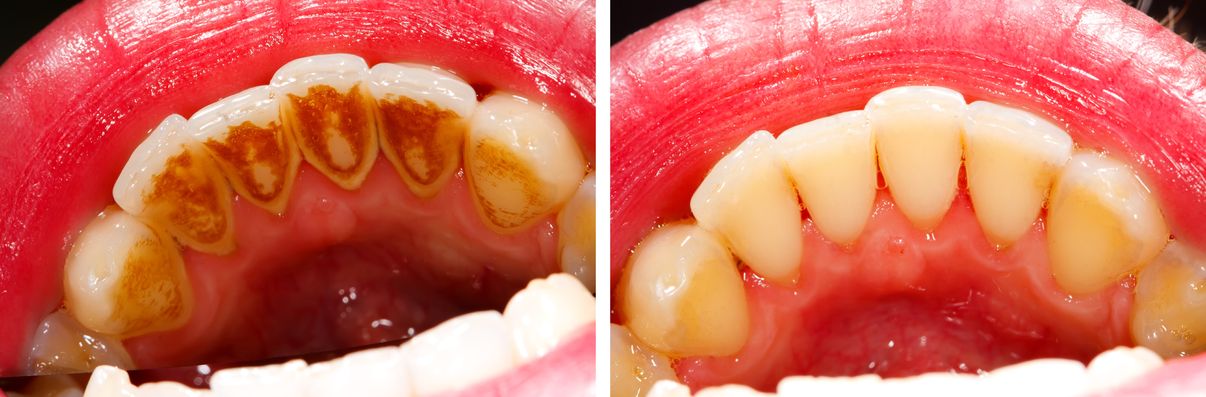

Lấy cao răng thực chất không có ảnh hưởng gì tới sức khỏe răng miệng. Trước kia khi thực hiện với khí cụ cầm tay thì việc lấy cao răng có thể gây kích ứng nướu, ê buốt răng sau khi lấy cao răng hoặc chảy máu một chút khiến rất nhiều người đặt ra câu hỏi lấy cao răng có hại gì không.???

Nhưng hiện nay, kỹ thuật lấy cao răng mới dùng sóng siêu âm của đầu dụng cụ scaler, làm rung lên để vôi bám vào men răng rớt ra, làm cho răng trở nên sáng hơn. Đây là kỹ thuật rất đơn giản, chỉ tác động vào mảng cao răng và làm bong ra khỏi răng mà không gây tổn thương cho lợi và răng.